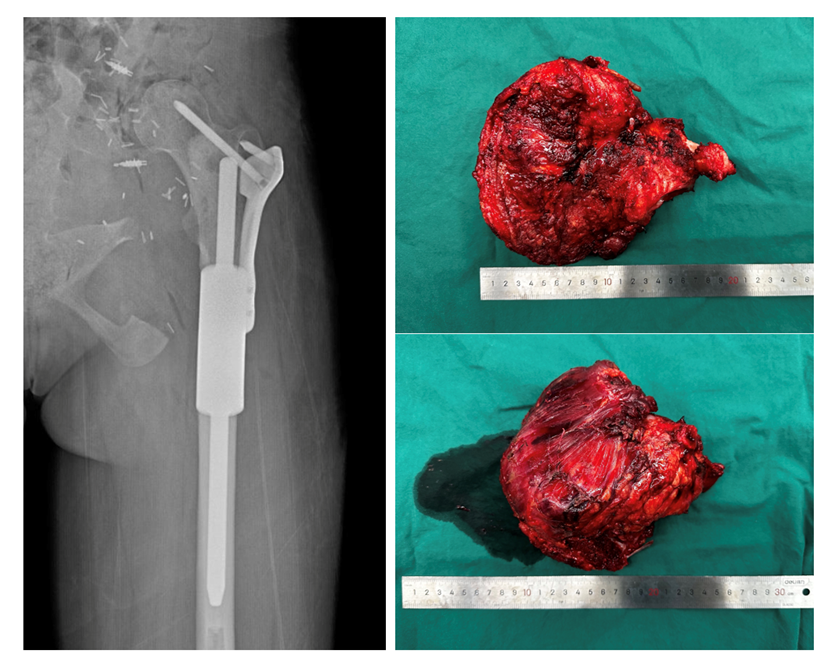

图:患者术后复片,骨盆肿瘤切除术后,假体位置良好;骨盆切除术后标本。